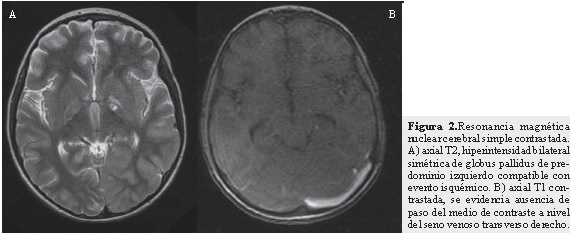

Se realizó Doppler arterial transcraneano y se encontraron, a nivel de arterias cerebrales medias, cambios compatibles con estado de hiperperfusión en las regiones izquierdas que pueden estar en relación con edema cerebral de ese lado. En la RNM cerebral simple y con gadolineo más angioresonancia se evidenció trombosis de senos venosos cerebrales profundos (parcial de seno longitudinal superior, completa de seno venoso transverso de predominio izquierdo, parcial a nivel de senos venosos sigmoideos y trombosis a nivel de la confluencia de los senos) (Figuras 1 y 3). Se evidenciaron accidentes cerebrovasculares (ACV) isquémicos venosos gangliobasales izquierdo y derecho, talámico izquierdo y hemisferios cerebelosos. Así mismo, se vio edema cortical en las regiones occipitales bilaterales y hemisférica izquierda por proceso de congestión venosa veno-capilar y se observaron áreas de necrosis laminar cortical fronto-parietales izquierdas. En la RMN cerebral de control hay evidencia de ACV isquémico en los globus pallidus bilaterales de mayor compromiso en región gangliobasal izquierda (Figura 2) y ACV isquémico en el mesencéfalo a nivel de los pedúnculos cerebrales de forma bilateral, sin evidencia de progresión de la trombosis con respecto a la RNM previa.